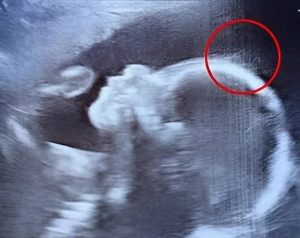

Un instantané échographique qui a ébahi l’équipe soignante

« Attendez… est-ce que je vois bien… une chevelure ? » lance-t-il, un mélange d’étonnement et de gaieté dans la voix. Un autre professionnel vient jeter un œil et plaisante en disant que ce petit être semble déjà faire son entrée remarquée. Sur l’écran, de fines mèches semblent danser doucement, créant une vision à la fois inattendue et profondément touchante.

L’équipe médicale se fait ensuite un devoir de rassurer Émilie : il est normal que la pousse des cheveux débute avant la naissance. Ce qui est extraordinaire, en l’occurrence, c’est la netteté avec laquelle on peut les distinguer et leur volume apparent à ce stade de la grossesse, des caractéristiques rarement aussi visibles lors d’une telle imagerie.